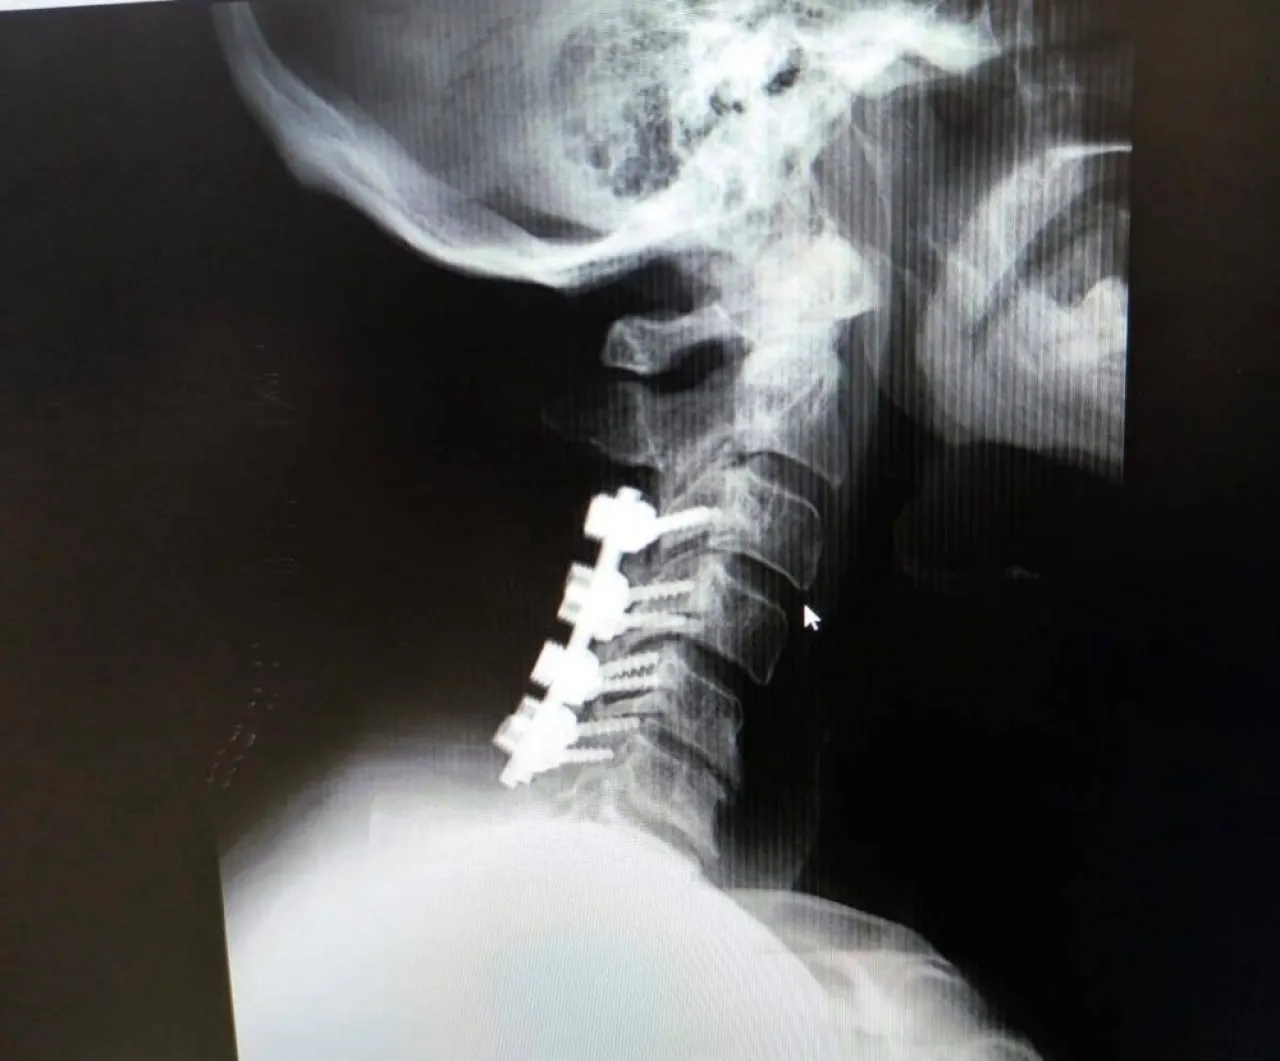

خبرني - أجرى فريق طبي جراحي متخصص في قسم جراحة الدماغ والاعصاب في مستشفى الكرك الحكومي عمليتين جراحيتين تعتبران من العمليات النوعية التي تجرى لأول مرة في المستشفى حيث اجريت العملية الاولى باستخدام تقنية التداخل المحدود لإزالة انزلاق غضروفي ضاغط في الفقرات القطنية، وتمثلت العلمية الجراحية الثانية بازالة ورم من عظم الجمجمة، وذلك وفق ما نشرته صحيفة الغد.